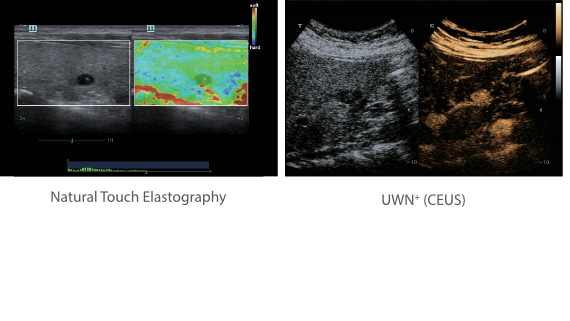

Sobre la base de un profundo conocimiento de las necesidades del cliente, el DC-60?ECHO con X-Insight estå dise?ado para brindar alta eficiencia con imågenes precisas, lo que se ve potenciado con eXpress Clarity (claridad exprés), eXceptional Intelligence (inteligencia excepcional) y eXceeding Experience (experiencia extraordinaria).

eXceeding Experience

Experiencia con alta productividad